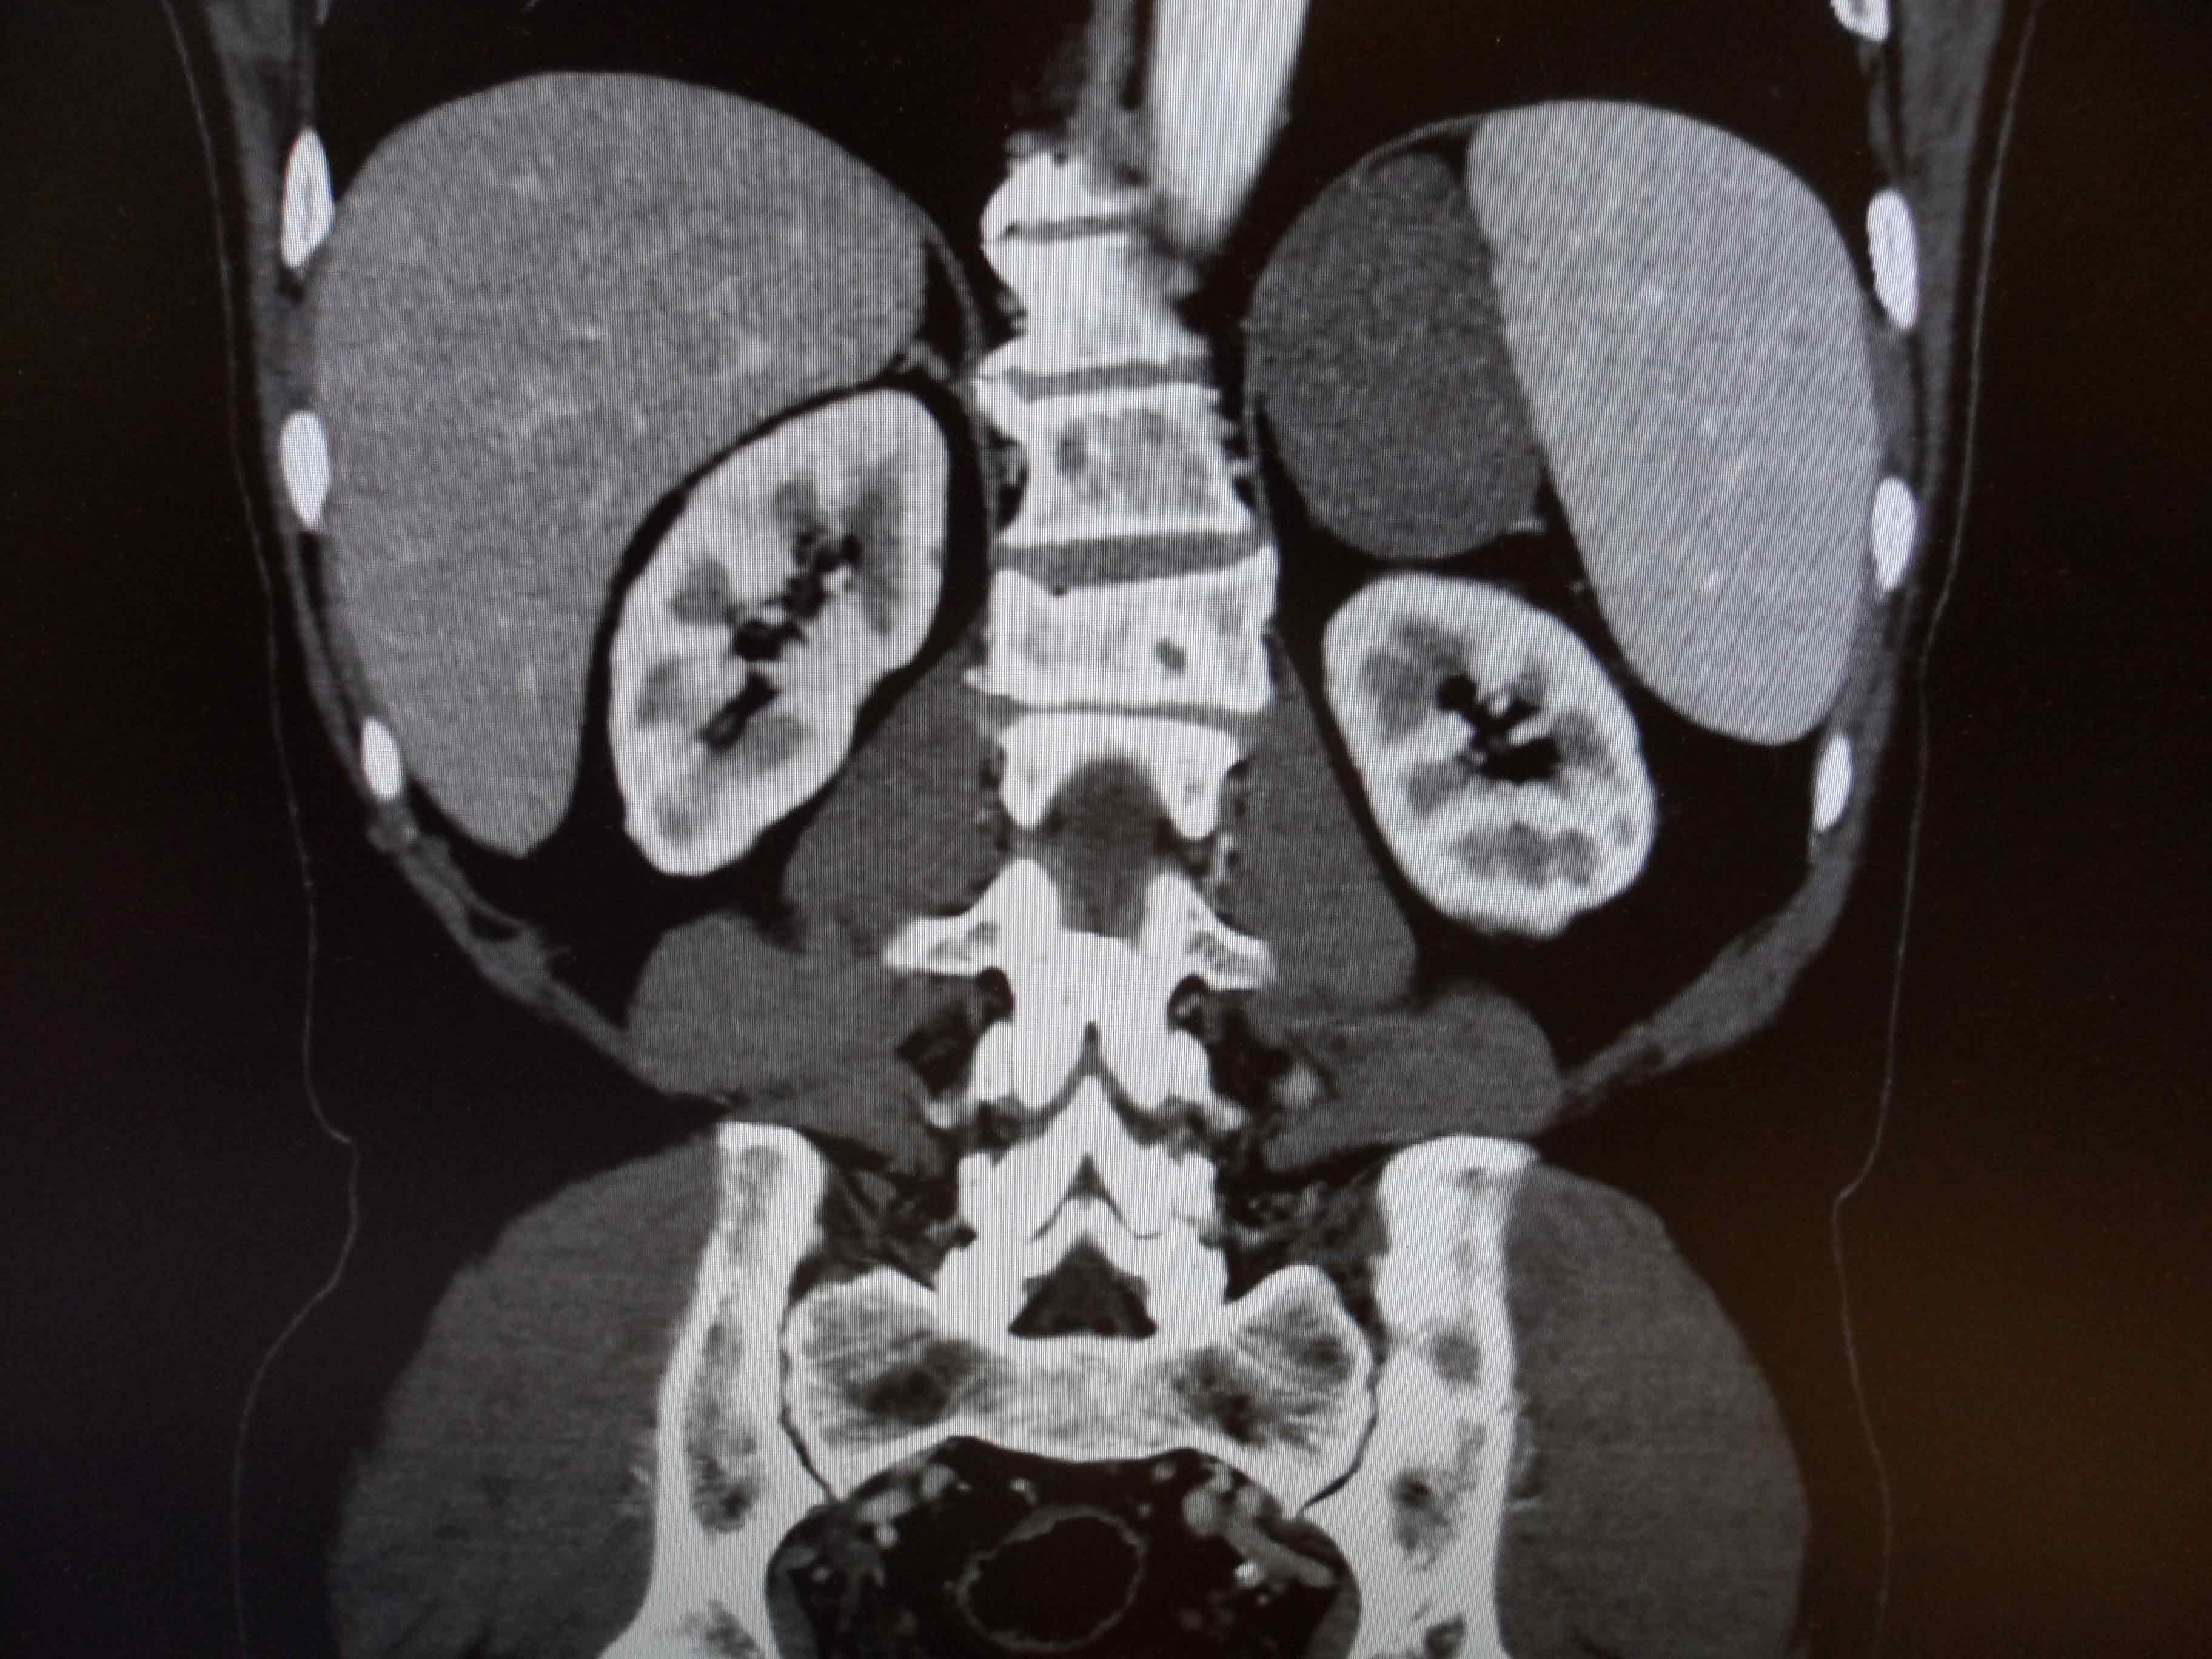

ºÎ½Å Á¾¾ç

»çÁøCT/MRI